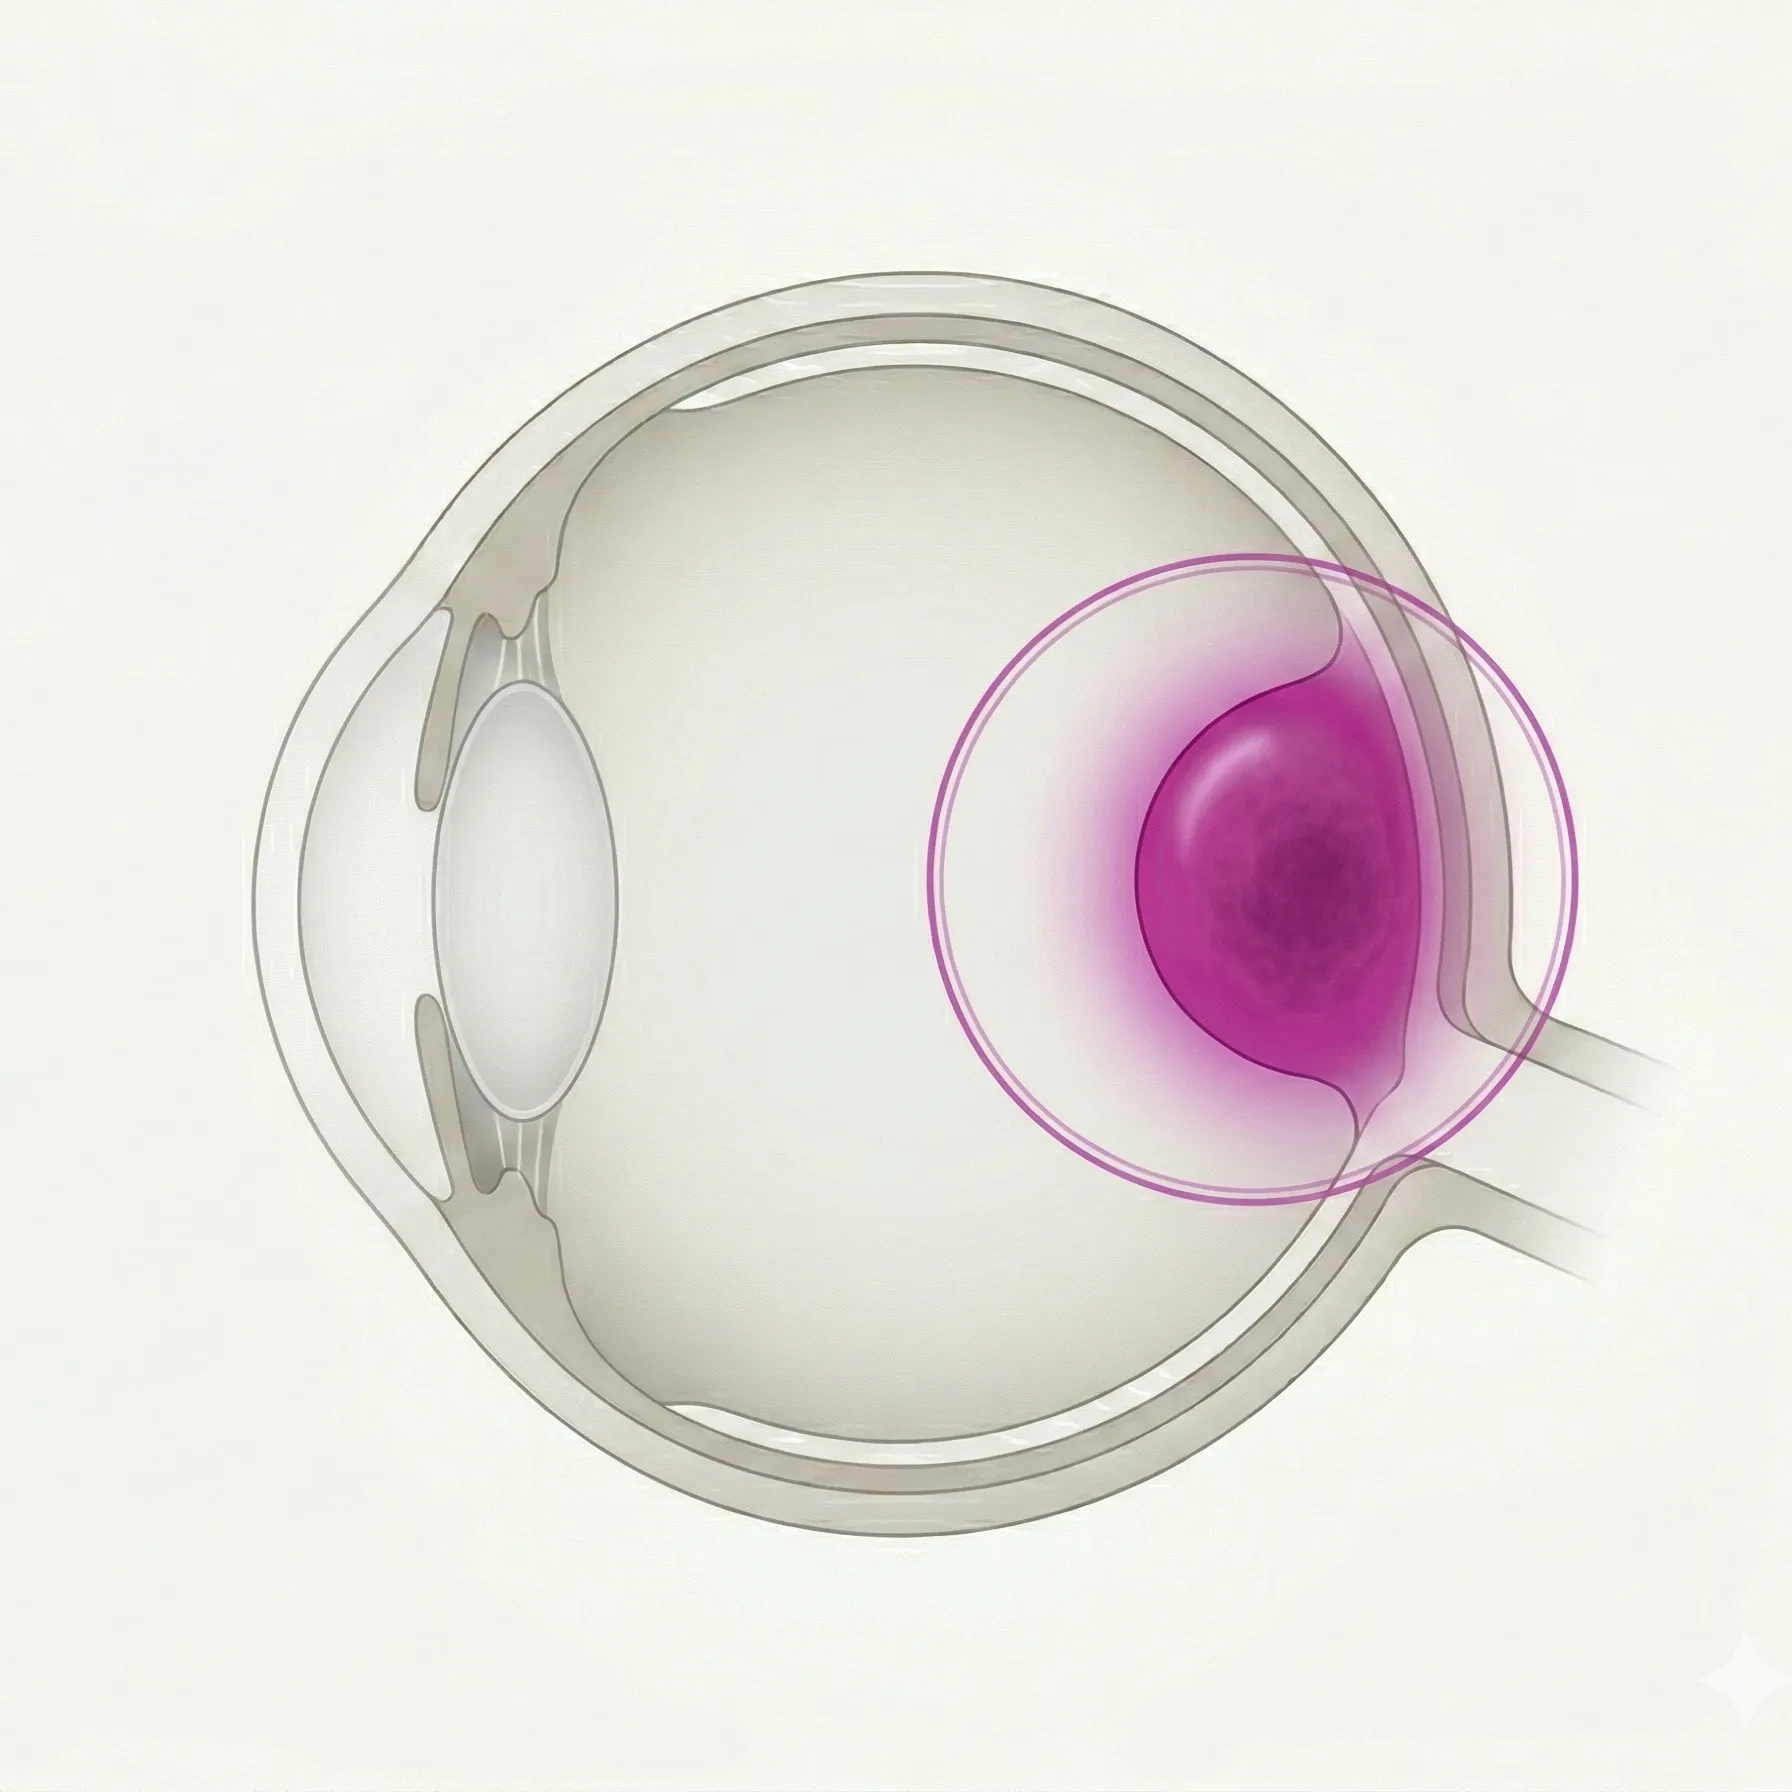

13件成人で最も多い原発性眼内悪性腫瘍であるブドウ膜メラノーマのうち、脈絡膜および毛様体から発生する後部ブドウ膜メラノーマについて、診断・治療・予後を解説する。

脈絡膜メラノサイト由来の良性色素性病変について、悪性転化リスク因子の評価(TFSOM-UHHD)と経過観察の方針を解説する。